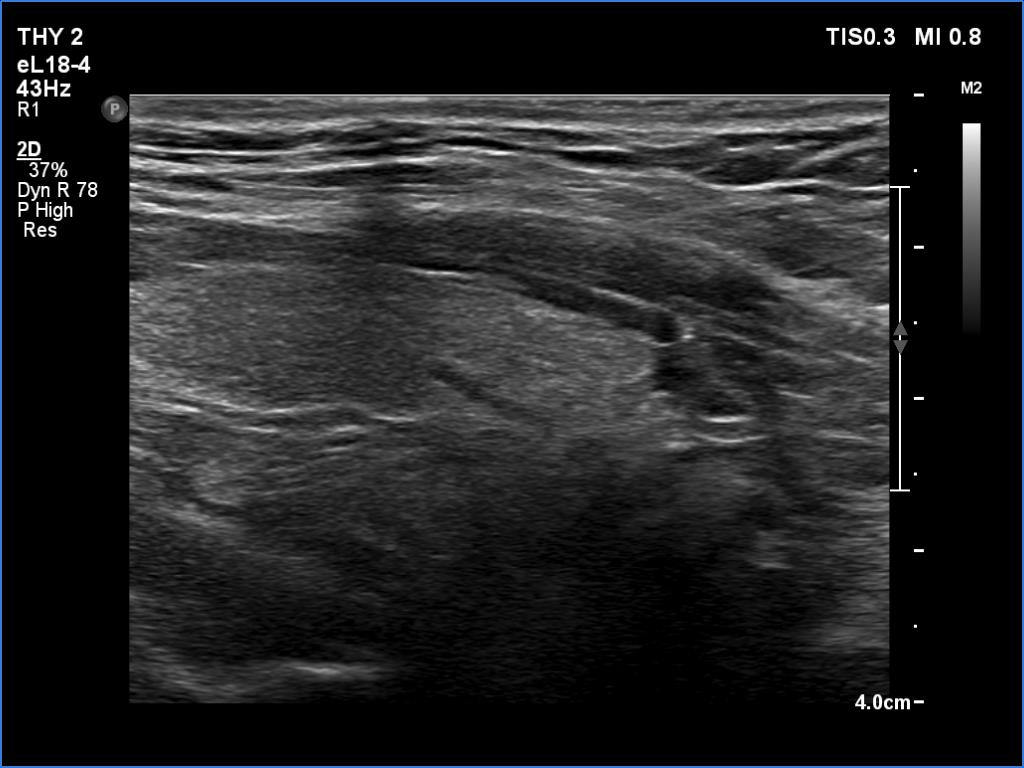

Ultrasonography. The thyroid was echonormal. There was a hypoechoic mass dorsal and under to the lower pole of the left thyroid lobe.